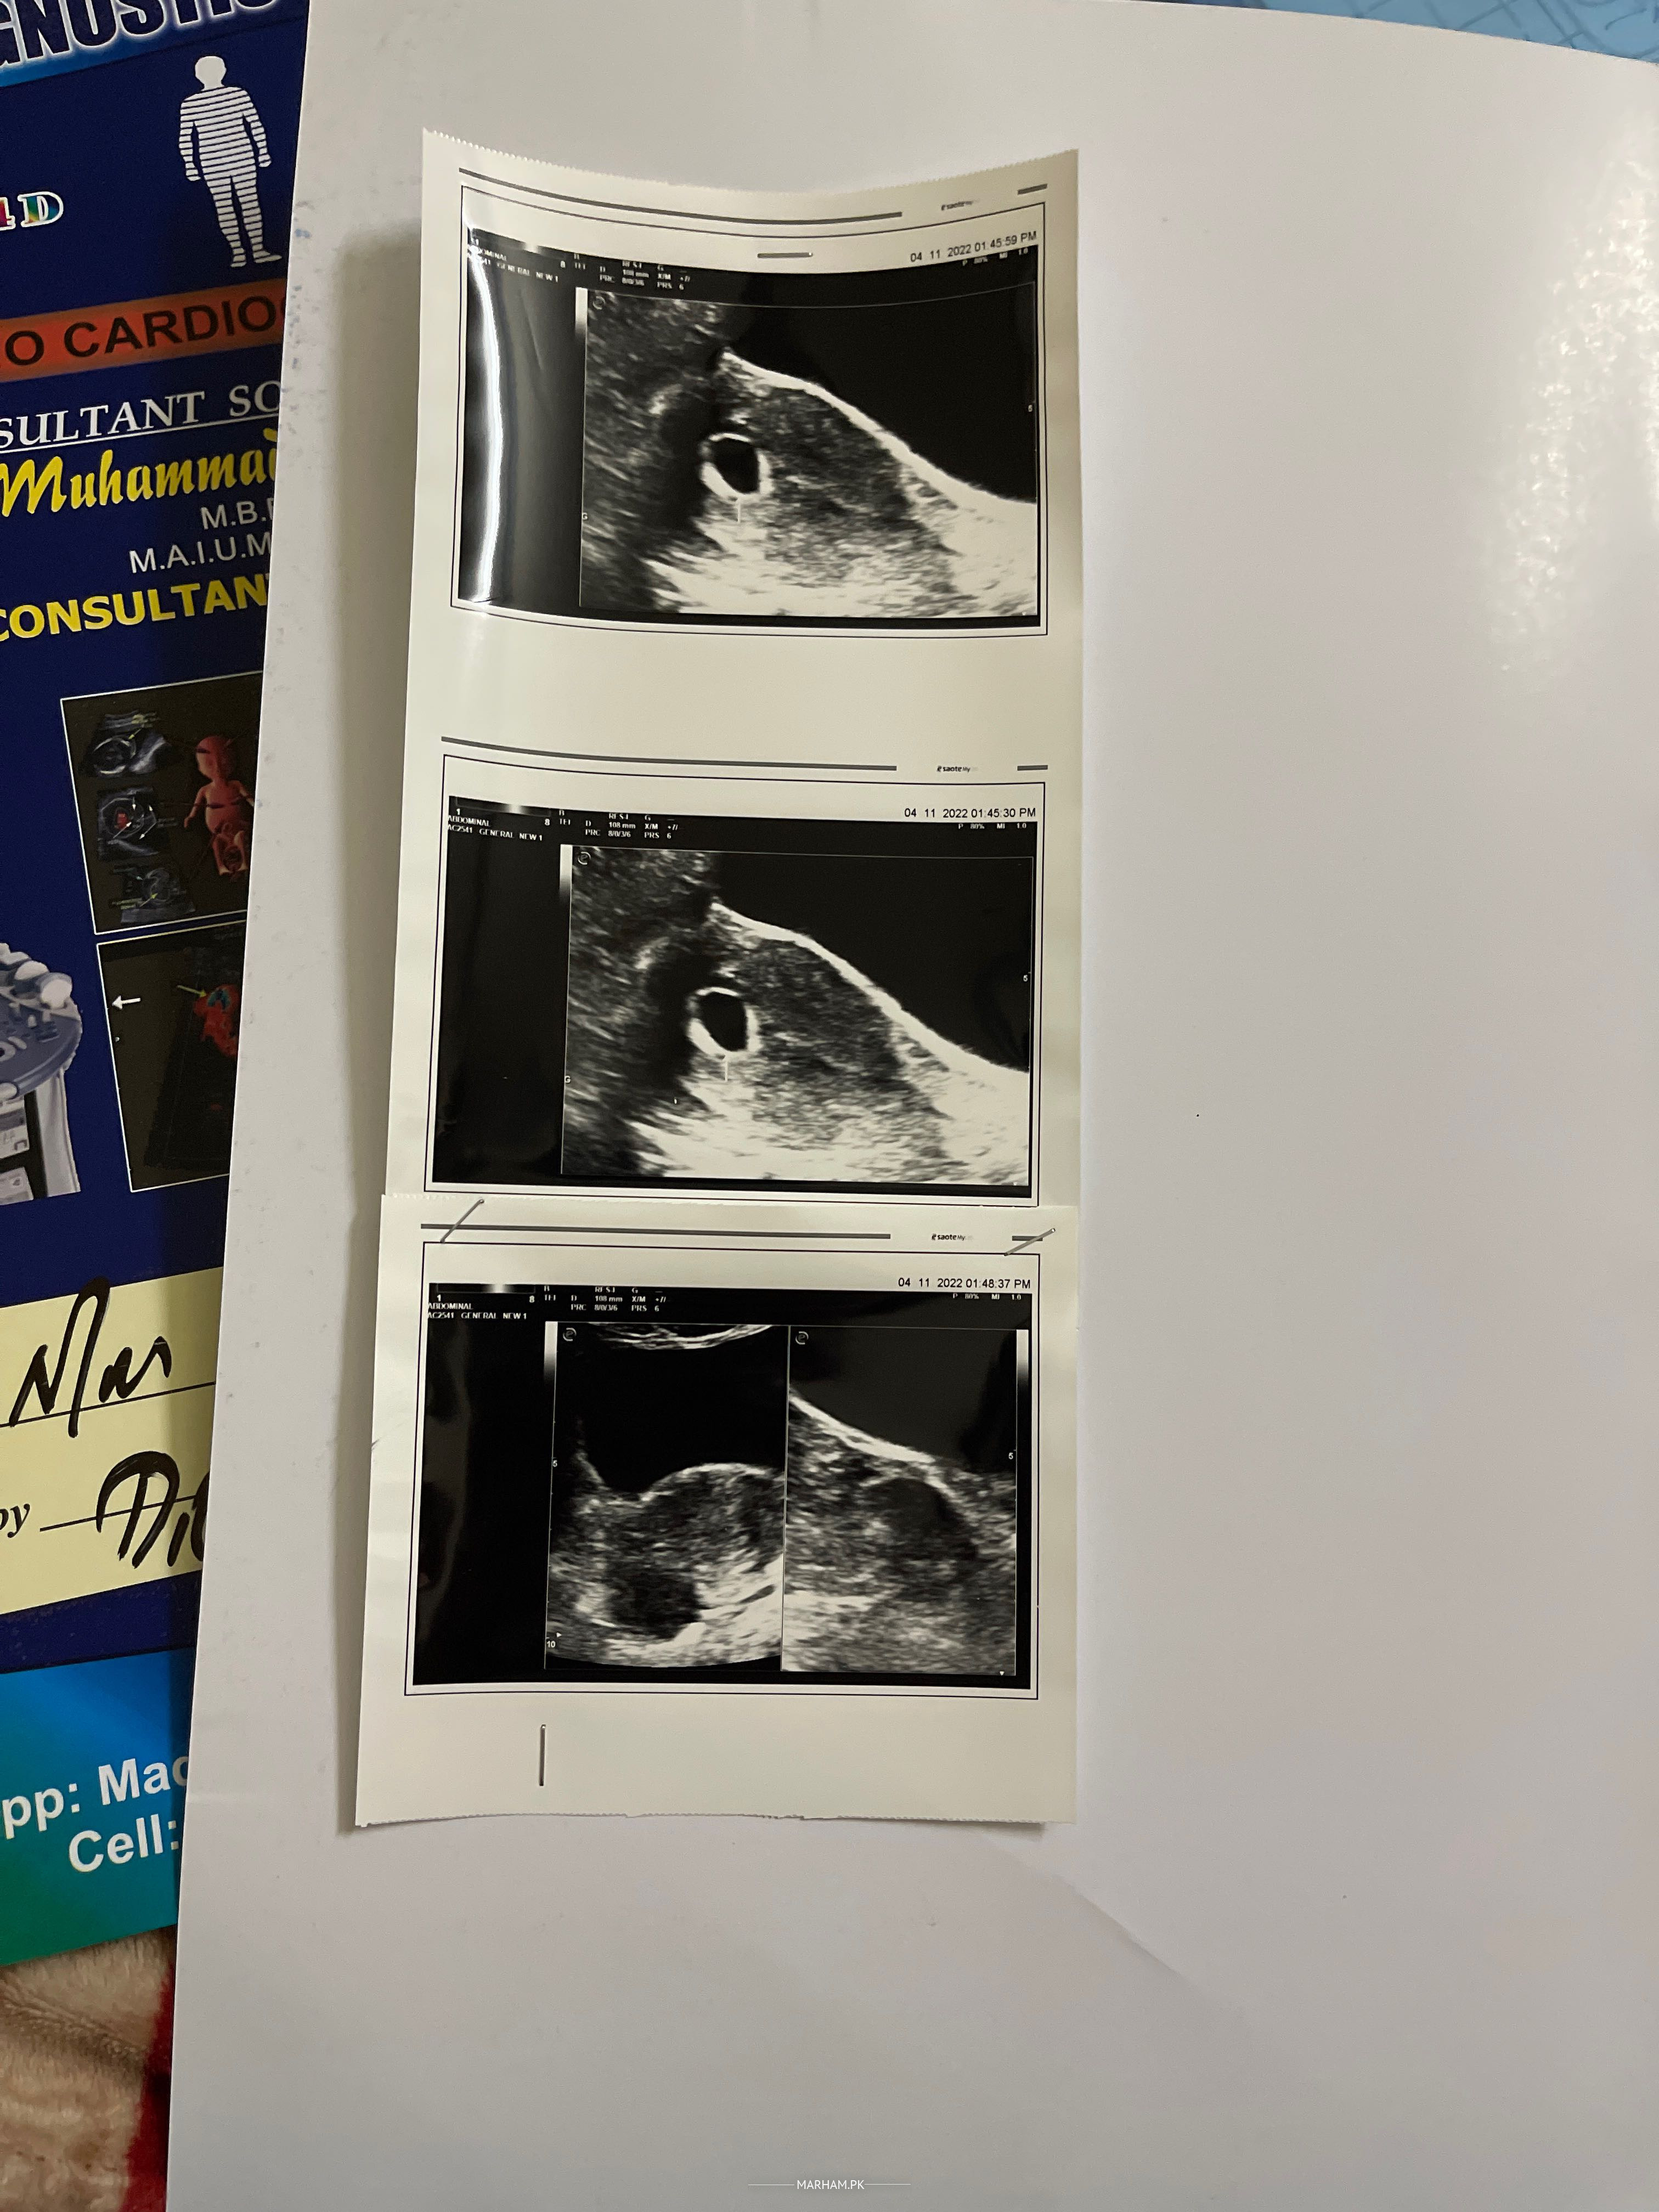

iam pregnant my last period date is 20 15 nov ko ultrasound krwaya to keh rhe k sirf sac hai bacha ni aur heartbeat wait kr rai hun kyun k meri family me late heartbeat b ayi hai ese cases hue help me can i do..

on ultrasound there is missed abortion...consult gynaecologist in person for history and further advice

most likely it's missed abortion ...u can wait for a week if u want ...but chances for viable pregnancy are less